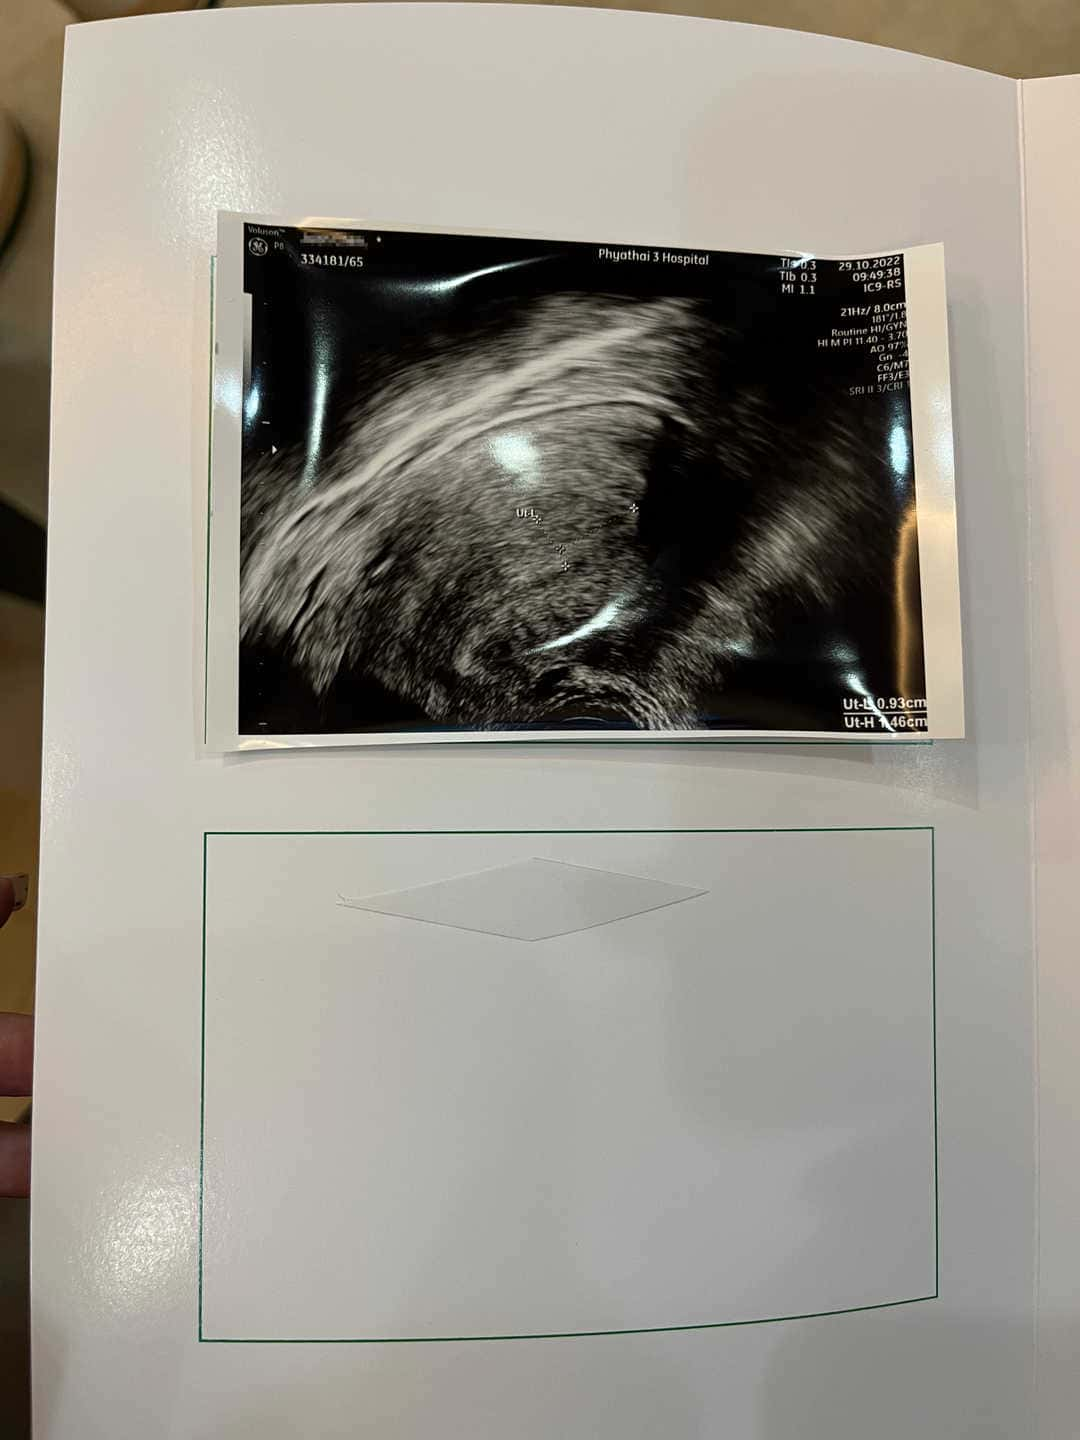

今天是患者移植前的第二次见诊 ~ 医生做阴超检看患者的子宫内膜情况今天内膜三线很清晰而且厚度也达到可以移植的达标了 因为患者定时的准时用药所以内膜长得很好 医生跟患者确认好了我们要移植几个胚胎 确定移植日期 给患者准备好了移植前后注意事项 而且还给患者开了我们关于孕酮的激素药 期待着下个星期移植顺顺利利 接好孕